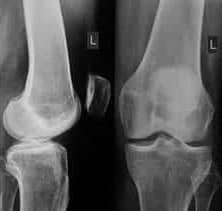

Artritis ialah salah satu masalah kesihatan utama penduduk, dan kadangkala ia dirujuk sebagai wabak milenium ketiga. Dalam tinjauan kebangsaan, kira-kira satu pertiga orang dewasa melaporkan sakit sendi dalam tempoh 30 hari yang lalu. Sakit lutut ialah aduan yang paling biasa diikuti oleh sakit bahu dan pinggul. Tetapi sakit sendi boleh menjejaskan mana-mana bahagian badan dari pergelangan kaki dengan kaki ke bahu dan tangan. Semakin meningkat usia, semakin sakit sendi menjadi biasa.

Ketahui simptom yang mungkin menunjukkan disfungsi dan penyakit muskuloskeletal:

Sakit dan terkehel pada sendi apabila bergerak

Kekakuan dan pergerakan terhad

Kemahiran motor halus terjejas

Kekejangan anggota badan yang kerap

Meteosensitiviti badan

Deformasi tulang dan rawan

Jika anda mempunyai sekurang-kurangnya satu simptom, terdapat 99% kemungkinan anda berisiko!